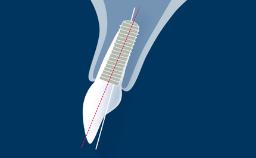

The replacement of missing teeth by means of dental implants has been proven to be a successful treatment modality for the rehabilitation of healthy patients, with long-term success rates of greater than 90%.

Therefore, this module provides a clinically relevant overview of local pathologic conditions that may have a bearing on implant therapy, but it is not an exhaustive compilation of all such conditions.